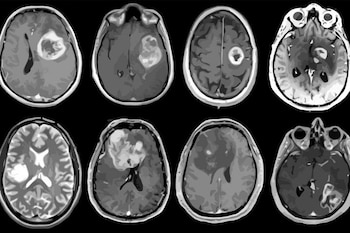

膠芽腫は、悪性脳腫瘍の中で最も一般的で致死性の高い腫瘍です。標準治療には、外科的切除、放射線療法、テモゾロミド化学療法の3つの現在の治療軸が含まれます。

しかし、治療の効力にもかかわらず、生存期間中央値は15ヵ月を超えず、診断から5年を超えて生存する患者はわずか10%である。

腫瘍細胞が周囲の健康な組織に侵入して浸潤する能力と、放射線化学療法に対する耐性のために、治療の有効性は限られています。この意味で、膠芽腫に対する現在の治療管理は、避けられない腫瘍の再燃に対する一時的な障壁に過ぎない。

膠芽腫腫瘍細胞の除去が困難